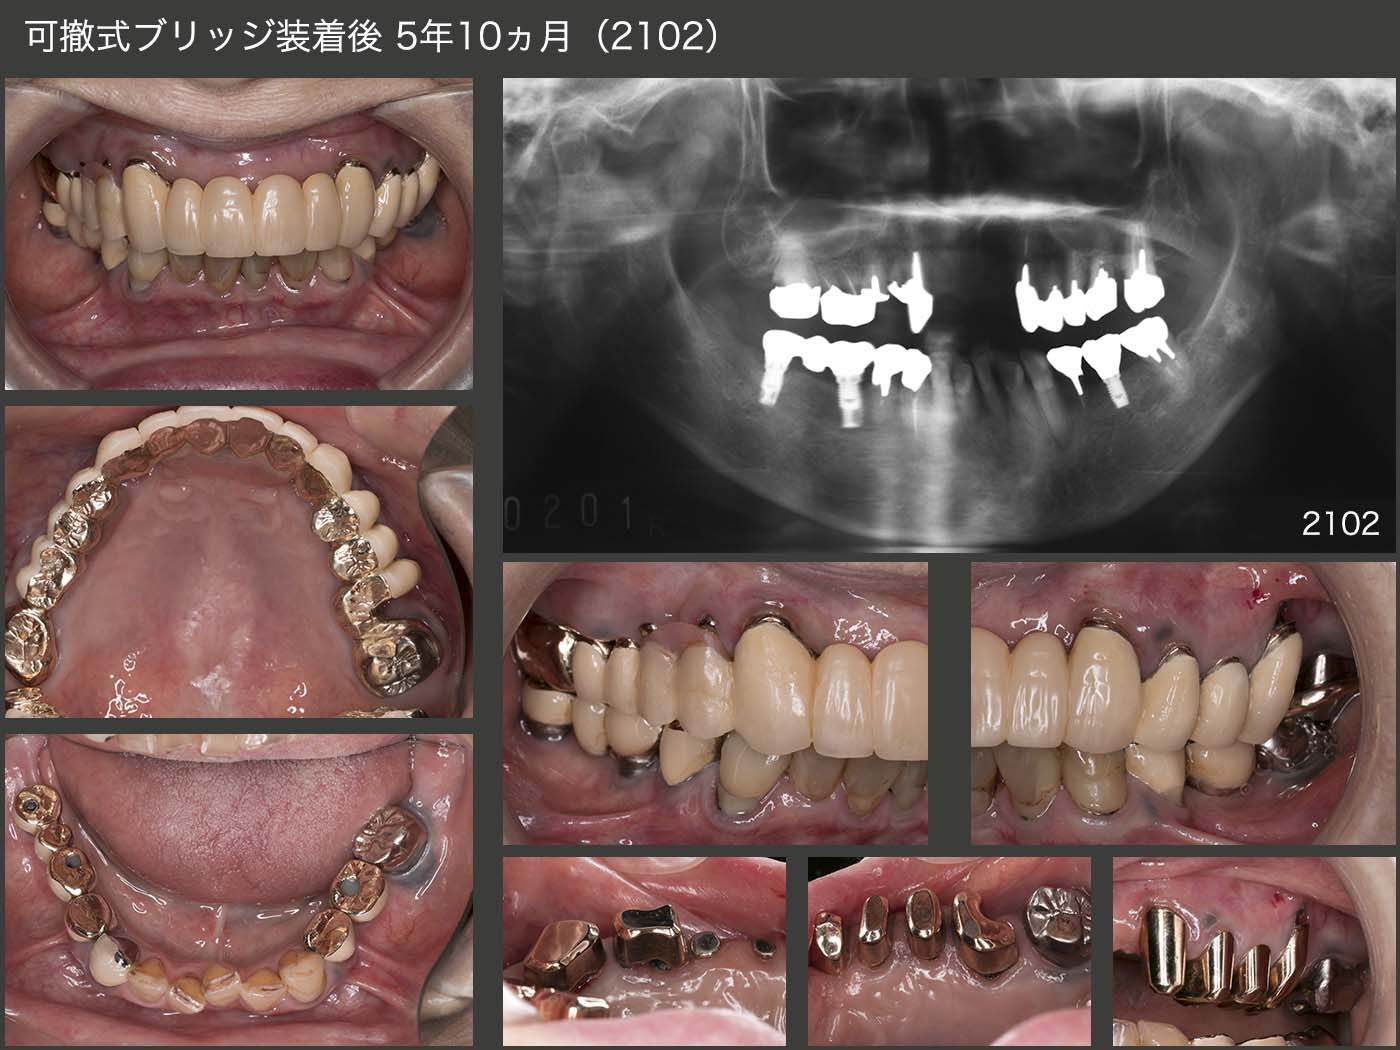

6.症例6

1994年初診,59歳の女性.主訴は下顎の義歯が合わないで,同年新規に製作した.また,95年7月から右上5から左上5のブリッジの新規製作に取りかかり,12月に完成した.スライド下のパノラマX線写真は,94年初診時および98年時の状態.

2014年1月,上顎ブリッジ製作後18年2ヵ月の状態.上顎は,一見問題なさそうであるが,パノラマX線写真から右上4,左上5に明らかなう蝕が認められた.また,右上3,4は,98年にコンポジットレジン修復を行ったが,完全にう蝕を取り除けたかどうか不安であった.このまま放置し,う蝕がさらに進行してしまうと,これらの歯を失う危険があることから,ブリッジの再治療を提案させて頂き,患者さんの承諾を得た.なお,下顎のインプラントは09年に施術した.この頃が私のインプラントの全盛時代であった.

まず,上顎左右3,7を残し,暫間義歯を装着した.ここで義歯に対する反応をみたのち,左右犬歯の冠も除去した.全体に歯肉縁下カリエスが認められたため,歯冠長延長術を施し,歯肉縁上歯質を確保した.

ここで,もう一度固定式のブリッジを装着することが可能であるが,暫間義歯に対する反応がよいことから,可撤式のブリッジ(コーヌス義歯)を選択した.審美性は,メタルボンドのブリッジより見劣りするが,外して清掃できるメリットは著しく大きい.また,将来どこかの歯にトラブルが生じても,補綴装置全体を作り直すことは殆どないと思われる.可撤式ブリッジ装着時の2015年4月の時点では歯肉が赤く,炎症がまだ残っていた.

2021年2月,可撤式ブリッジ装着後5年10ヵ月の状態.歯肉は大分健康になり,歯周ポケットは一番深い所で6mmの値であった.患者さん自身も可撤式ブリッジにして本当に良かったとおっしゃっている.

しかし,根面カリエスが多発している.とにかく,甘味特にクッキー,ケーキが大好物とのこと.患者さんなりに一生懸命にブラッシングしているのは分かる.年齢も86歳.ある程度は仕方ないと考えている.とりあえず,サホライドを塗布し,グラスアイオノマーセメントにて充塡した.